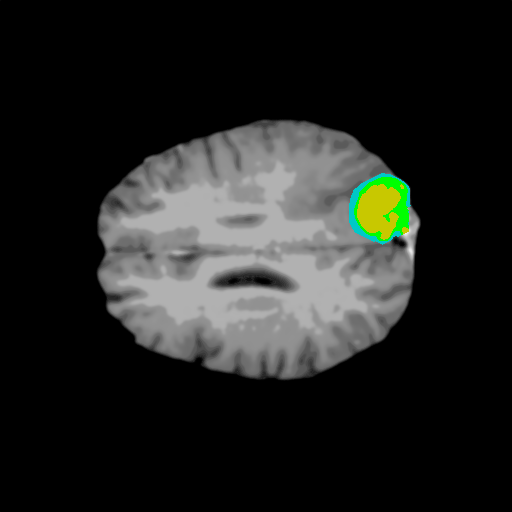

Extensive experiments have been performed in the current setup, and experimental outcomes are reported with the demonstration of numerical and statistical analyses using the proposed QFS-Net, QIS-Net [39], convolutional U-Net [18] and Residual U-Net (URes-Net) architectures [20]. The human expert segmented skull-tripped contrast enhanced DSC brain MR input image slices of size and ROIs are provided in Figure 5 as samples. The demonstration of QFS-Net segmented images followed by the essential post-processed outcome on the slice no. for class level with four distinct activation schemes () are shown in Figure 6. It is evident from the experimental data provided in Table LABEL:tab1 that the proposed QFS-Net performs optimally for the -connected quantum fuzzy pixel information heterogeneity assisted activation () with and gray scale set in comparison with other thresholding schemes and gray scale sets under the four evaluation parameters () [44]. The segmented tumors obtained using the proposed self-supervised procedure under class transition levels with four different thresholding schemes , , and are demonstrated in Figures 7- 8 for the class boundary sets and [39], respectively. The segmented images using the remaining two class boundary sets ( and ) [39] are provided in the supplementary materials section. The segmented ROIs describing the whole tumor region after the masking procedure using QIS-Net, U-Net and URes-Net are also reported in Figure 9.